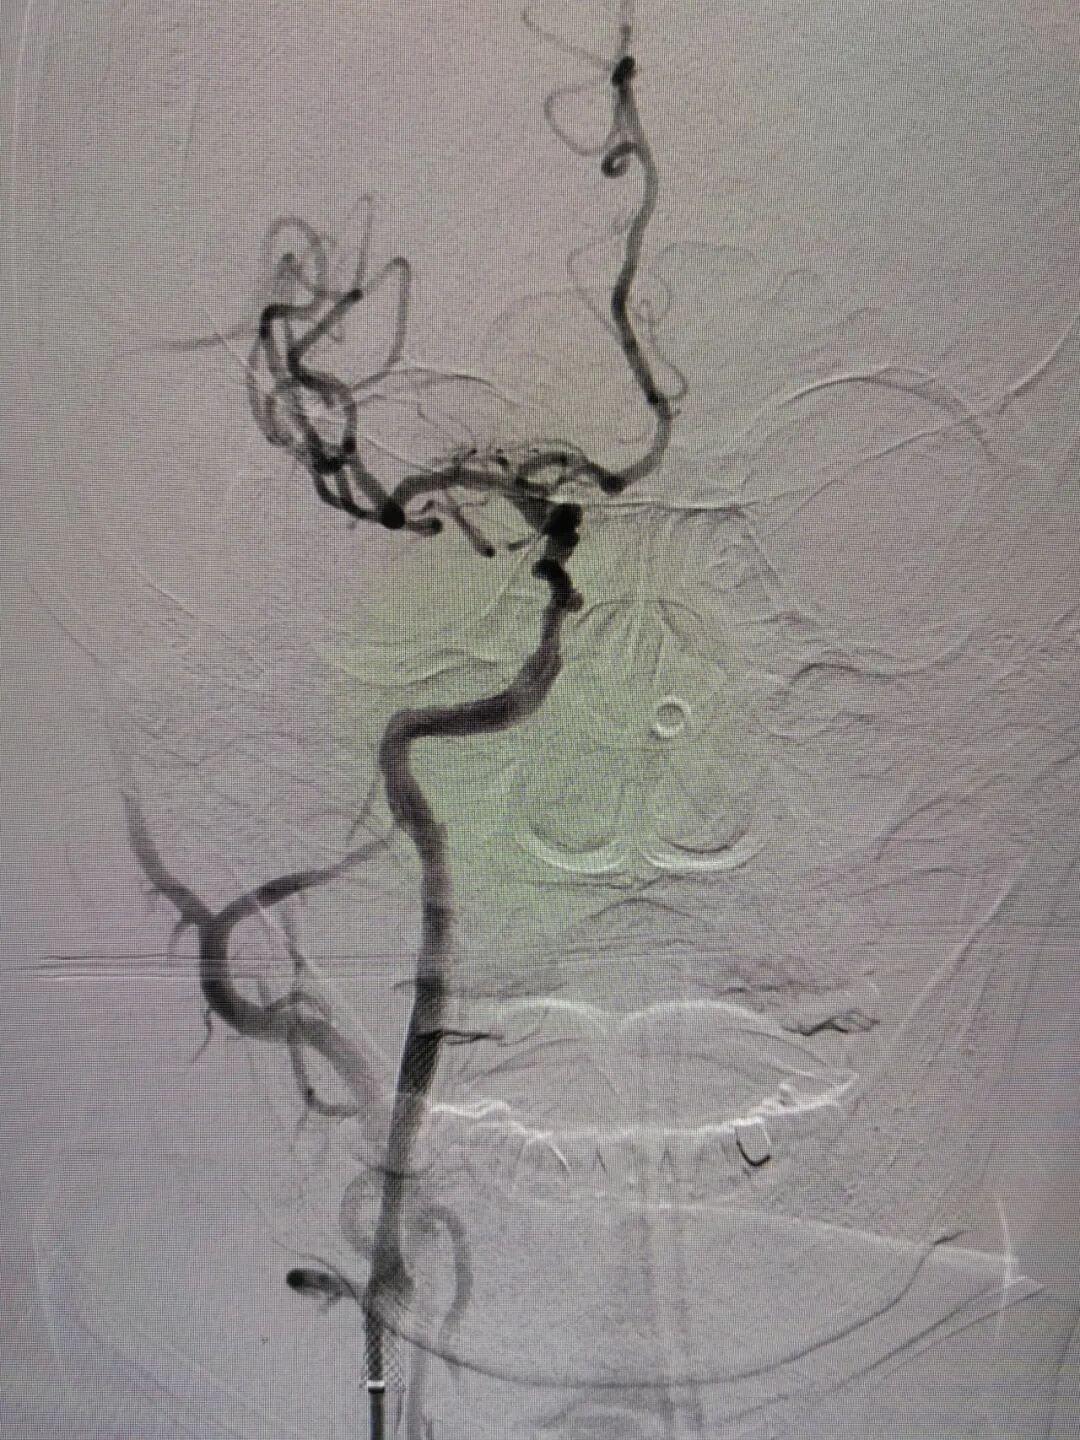

手术过程

经右侧桡动脉穿刺置入7F 薄壁鞘,畅医达 Calvada 5F 内腔0.072'' 导管鞘同轴125cm 5F 西蒙Ⅱ导管,在0.035'' 导丝引导下顺利到达右侧颈总动脉远端,小球囊预扩后,送入5mm 保护伞,4.0mm×30mm 球囊扩张后置入7mm×40mm 颈动脉支架。